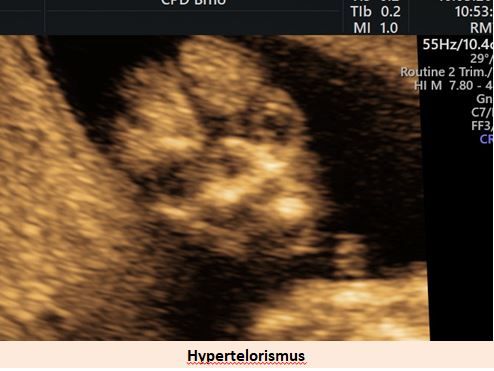

patří mezi nejznámější syndromy způsobené chromozomální aberací. V klasické formě je způsoben trizomií chromozomu 21. Je nejčastější vrozenou příčinou mentální retardace. Charakteristickými znaky jsou typický vzhled a srdeční vady .

Ultrazvuková diagnostika se při screeningu v 1. trimestru opírá o šířku podkoží v záhlaví plodu, osifikaci nosní kůstky a nálezu abnormálních průtoků v srdci plodu (trikuspidální regurgitace, reversní tok v ductus venosus).

Pracoviště se zkušenostmi v prenatální diagnostice a s dobrým přístrojovým vybavením je schopno vyslovit podezření na tento syndrom ve více jak 90% případů již při ultrazvukovém vyšetření ve 12-13. týdnu těhotenství. .